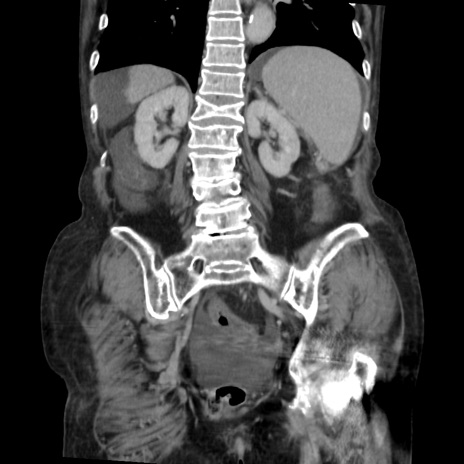

症例31(冠状断像)

【症例】80歳代 女性

【主訴】腹部膨満感

【現病歴】他院にて肝硬変にてフォロー中。1週間前から便秘、腹部膨満感、臍部腫瘤あり受診となる。

【既往歴】肝硬変

【身体所見】腹部膨隆あり、皮膚変化なし、疼痛なし。

【データ】WBC 4600、CRP 0.25